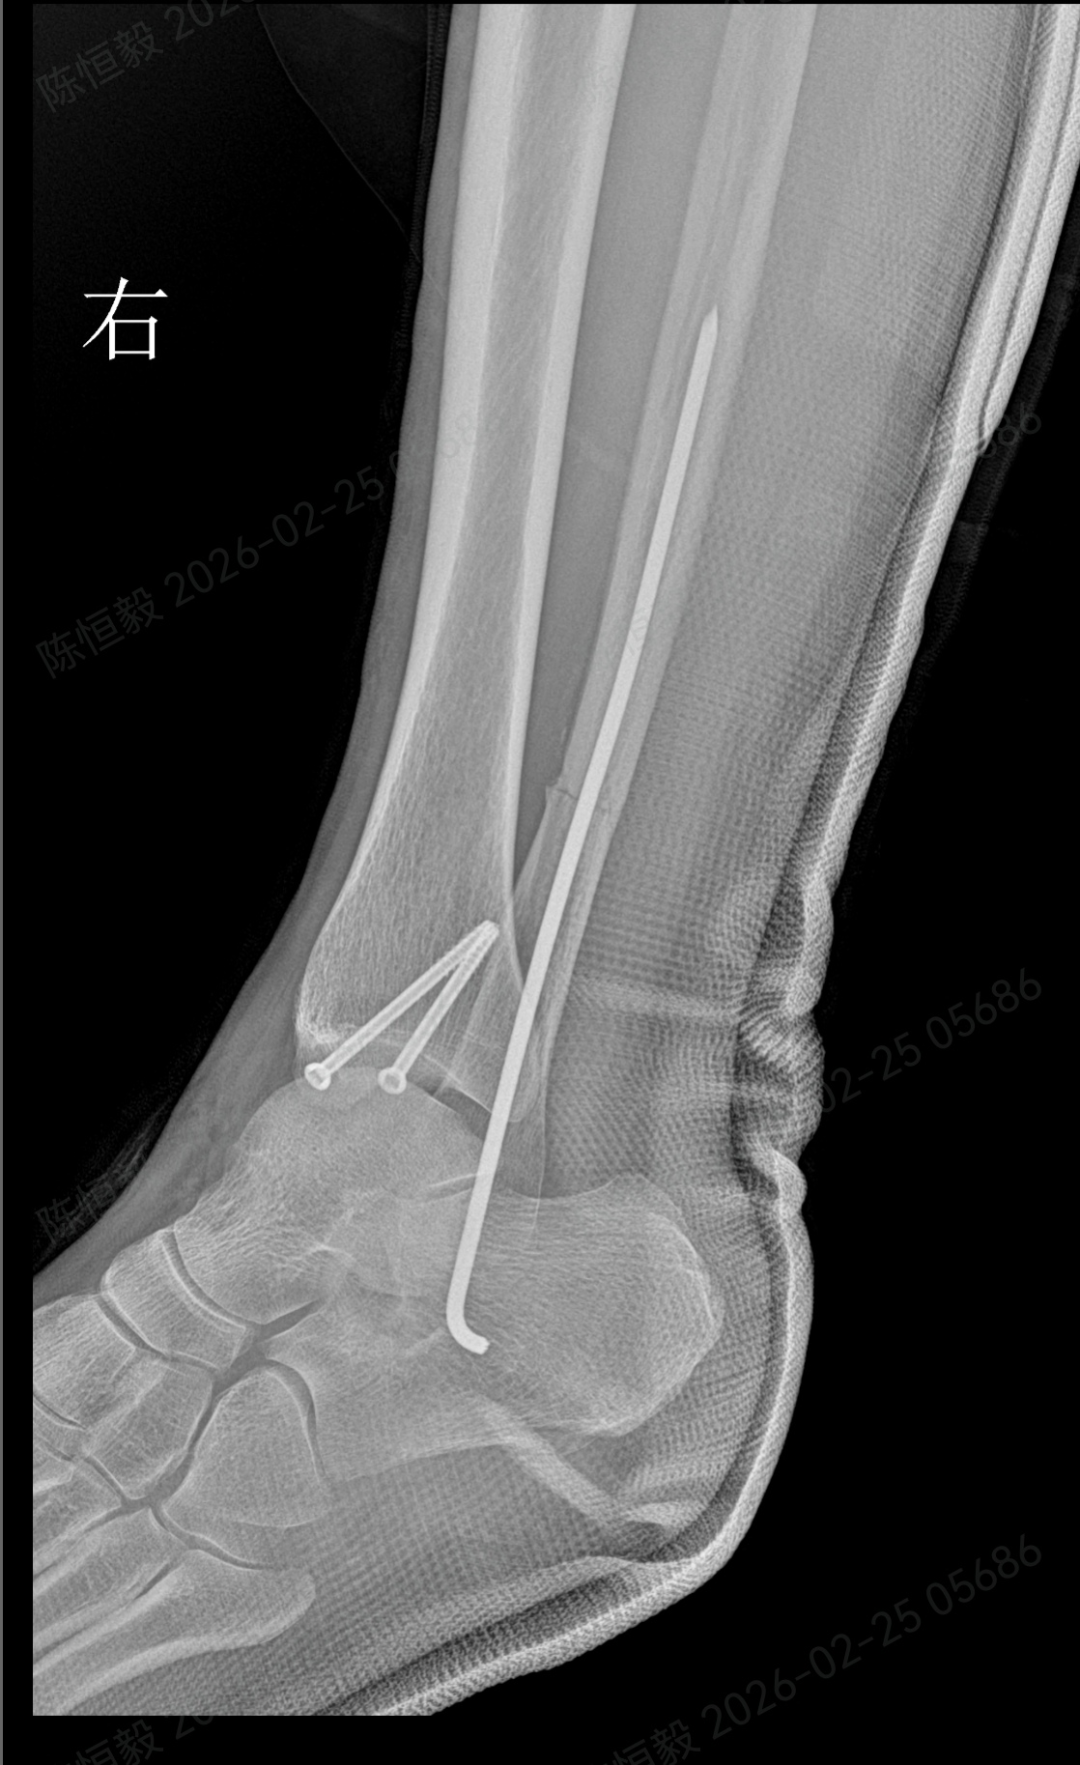

针对王女士的踝关节骨折情况,由副主任医师陈涛主刀,足踝外科团队为其实施了关节镜辅助下机器人导航微创闭合复位内固定术。

依托机器人导航系统,规划螺钉置入通道,避开关节面与重要组织;

最后通过另外两个 5 毫米的小孔置入空心螺钉,完成骨折端的稳定固定。

整个手术仅通过三个 5 毫米的小切口完成,最大程度降低了手术创伤。